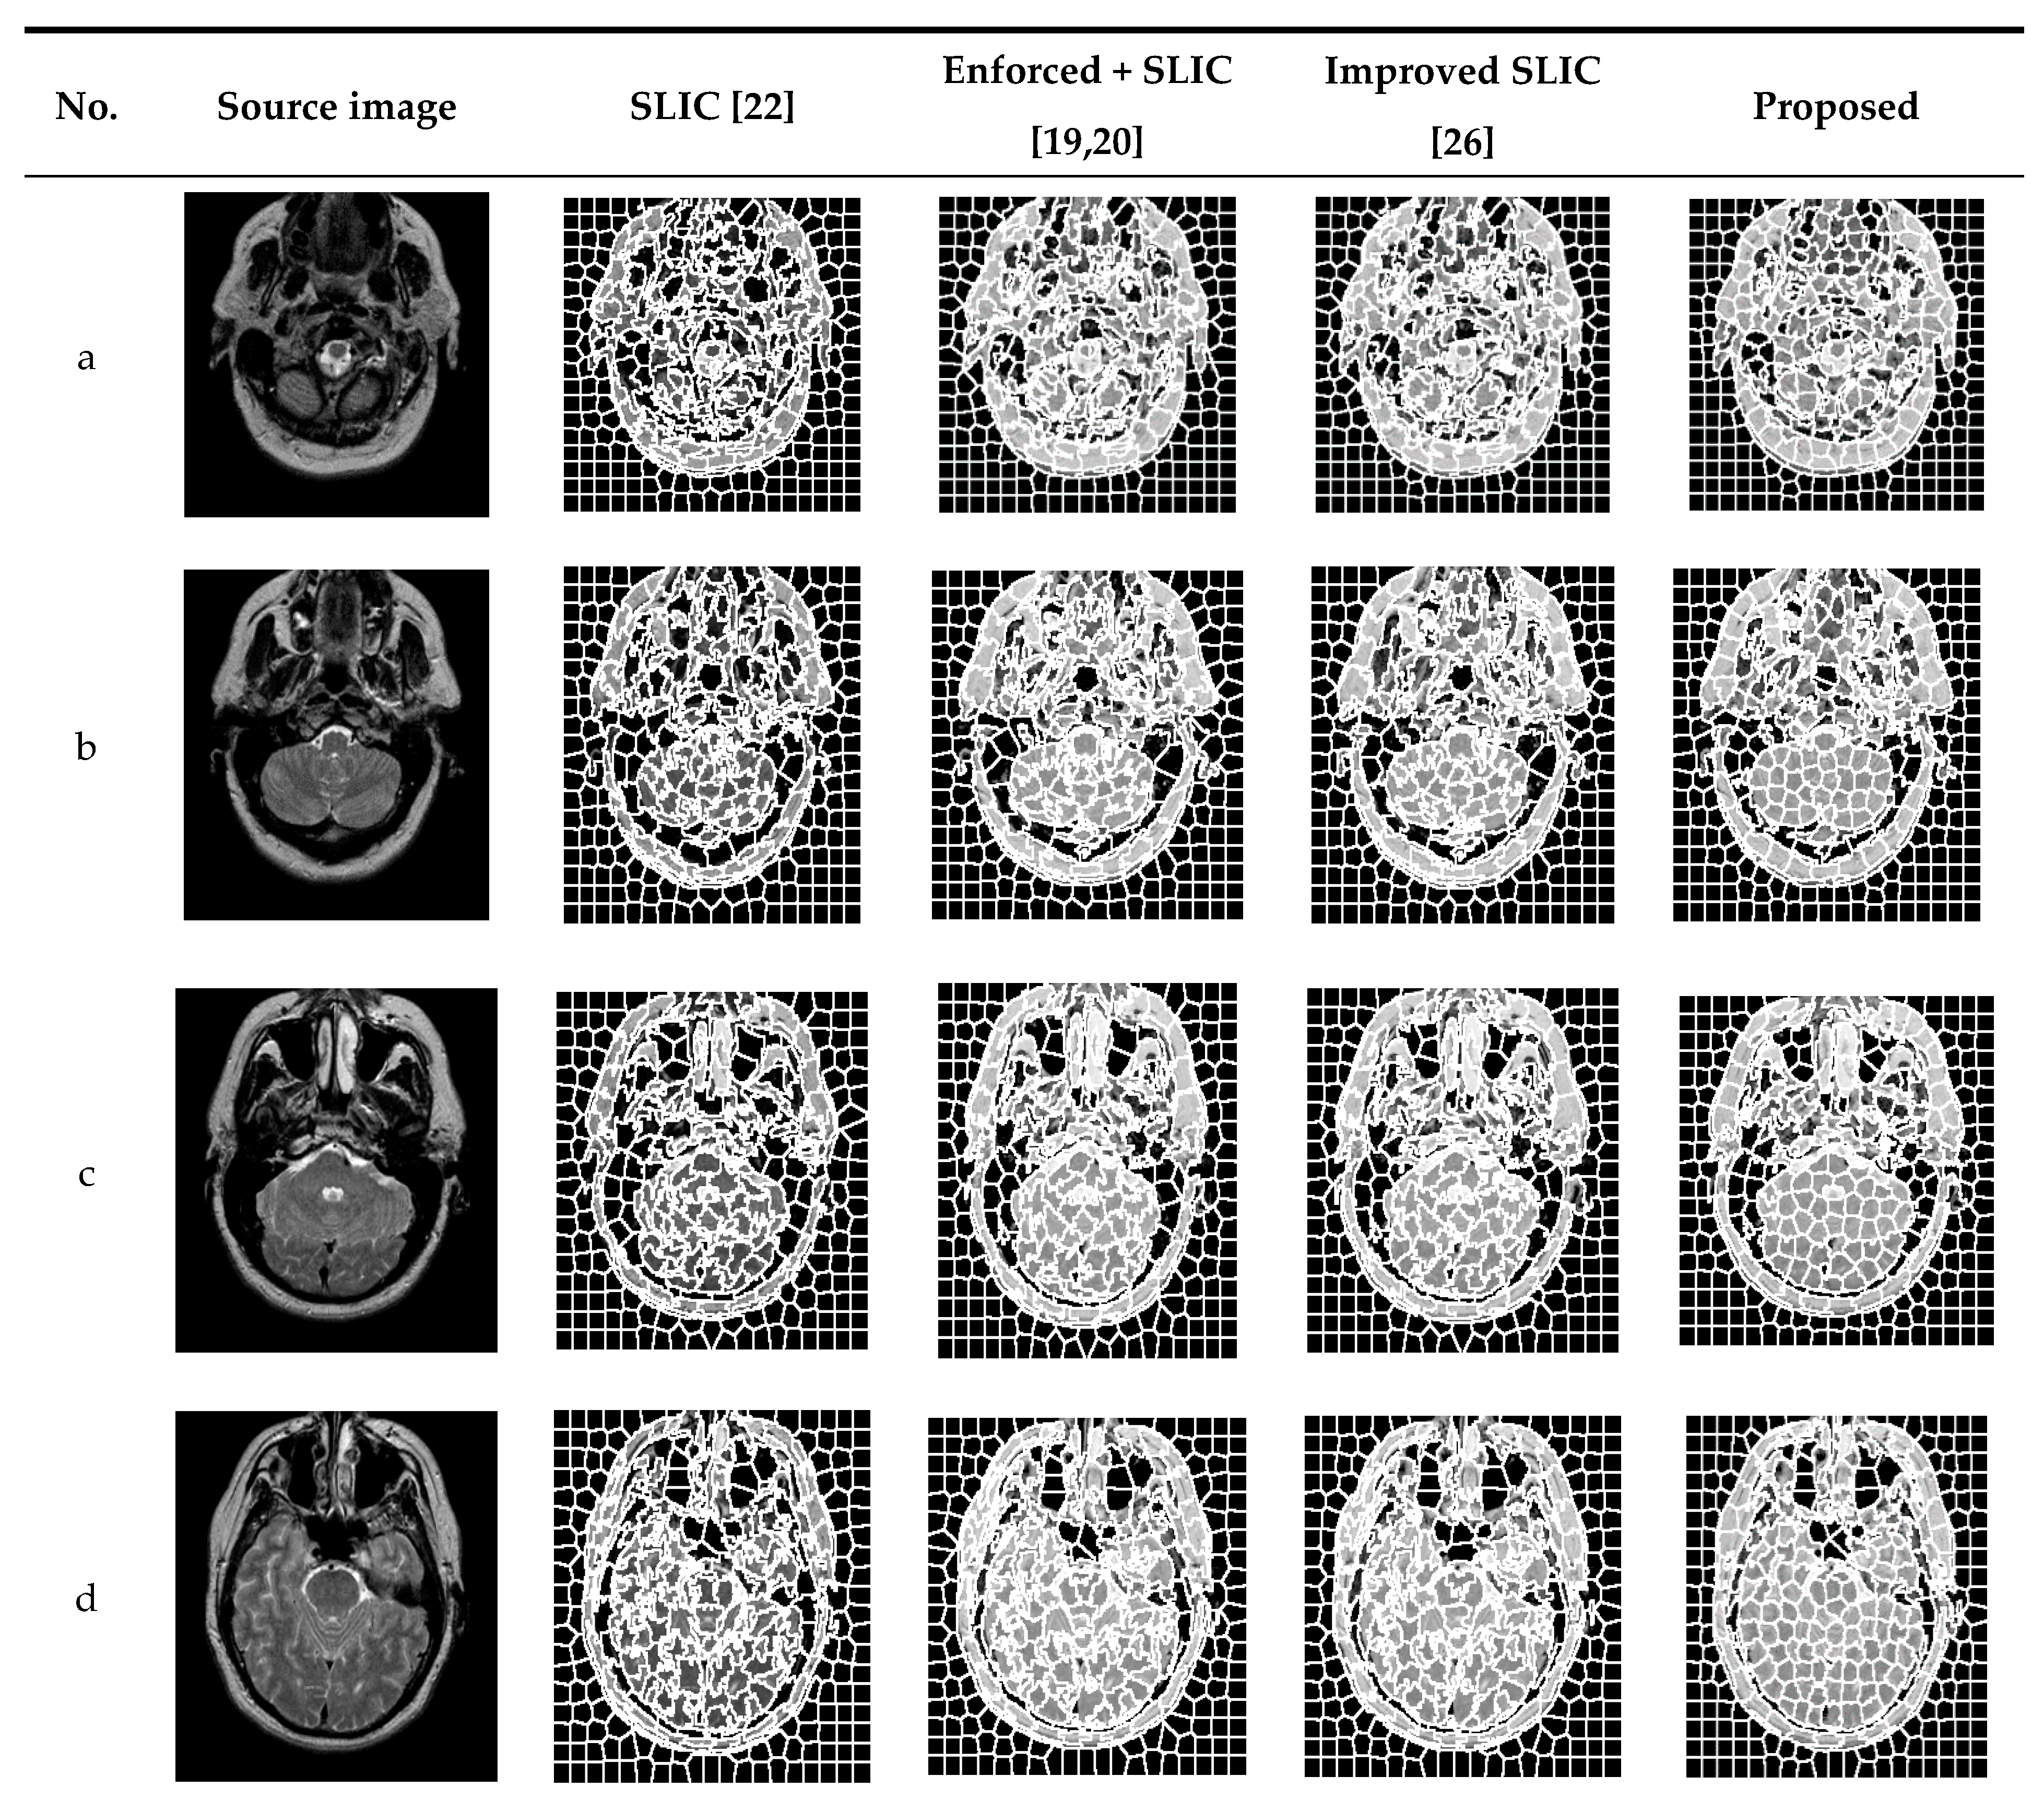

In order to verify the effectiveness of the proposed algorithm, experiments were carried out on several MRI brain images and were compared with traditional SLIC and enforced + SLIC algorithms. Figure 5 shows the segmentation results of traditional SLIC, enforced + SLIC, improved SLIC, and the proposed algorithm in this paper. As shown in Figure 5, after preprocessing, the target areas that are close to the color of the background area are segmented, the gray value consistency of the superpixel blocks is better, and the segmentation results are more accurate.

Figure 5.

The segmentation results of different algorithms.

Compared with SLIC, improved SLIC greatly improved the accuracy of superpixel segmentation and the consistency of superpixel blocks. As can be seen from Figure 5, after adding the local texture features of the image, the image features are better when calculating the similarity between pixels, and the pixels grouped into the same superpixel have more similar features. The superpixel edge of the proposed algorithm coincides with the edge of the target area in the image. The target areas close to the gray value of the background area and the smaller target areas that are misclassified are also significantly reduced. The superpixel blocks are more uniform and regular, and the accuracy of superpixel segmentation and the consistency in the superpixels are further improved in the proposed algorithm.